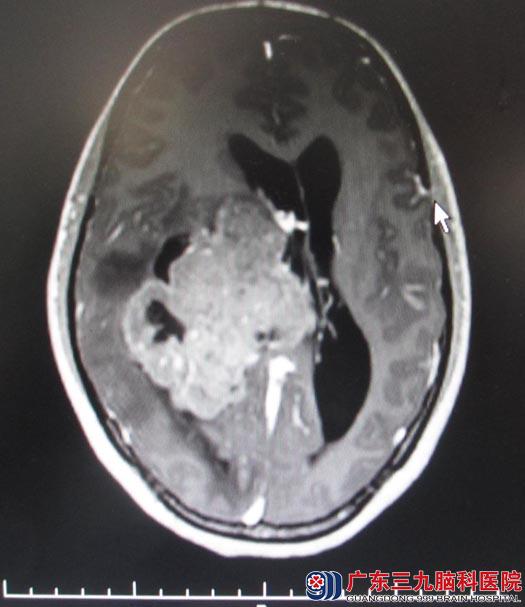

四月份曾在广东三九脑科行颅脑MR检查,示:右侧侧脑室三角区巨大占位性病灶,考虑肿瘤性病变。后入住综合神经外科,复查颅脑MR显示:1、右侧侧脑室三角区及周围巨大占位病灶,大小约7cm×9cm,考虑室管膜瘤、中枢神经细胞瘤或PNETs(原始性神经外胚层瘤)可能;2、右侧大脑镰下疝,右侧海马钩回疝,小脑扁桃体轻度下疝;3、空泡蝶鞍。肿瘤挤压对侧脑室,中线左移。